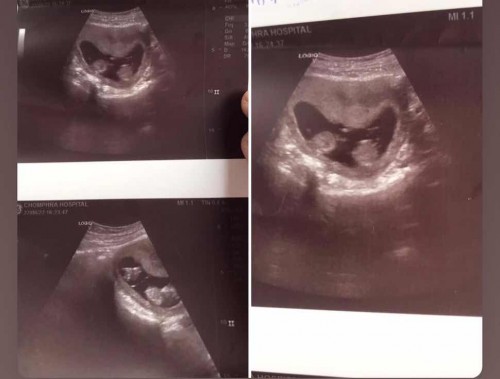

แบบนี้ลูกแฝดไหมค่ะ พึ่งท้องแรกค่ะ.

ซาวด์ตอน 11w.

แฝดคะ แบบนั้น บ้านนี้ก็ได้แฝดชายค่ะ30+3วีคแล้วตอนนี้

แฝดคร้า ยินดีด้วยนะคะ

ใช่ค่ะ ยินดีด้วยนะคะ

หมอบอกได้ลูกแฝดค่ะ. แต่คนเเถวบ้านไม่เชื่อ ค่ะ